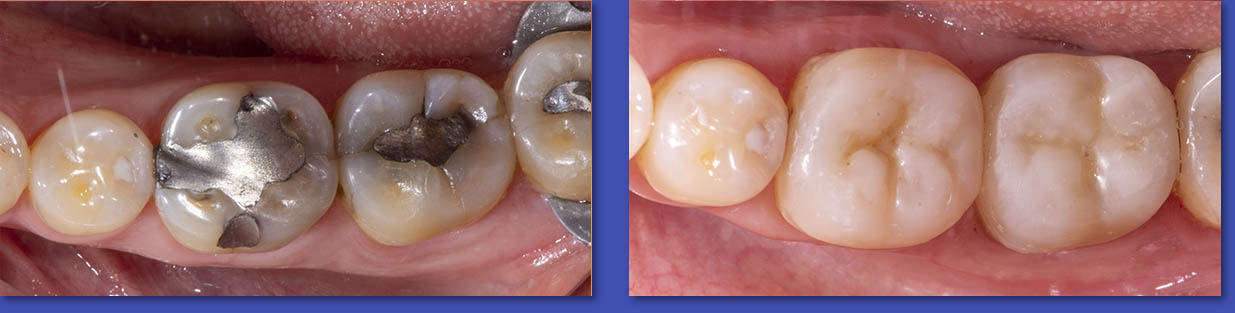

4. ORTODONCIA

La Ortodoncia se encarga del tratamiento de las anomalías de forma,posición,relación y función de las estructuras dentomaxilofaciales. La causa más común para el uso de aparatos de ortodoncia son las malposiciones dentarias o “ dientes chuecos “.

Ortodoncia

ANTES

DESPUÉS